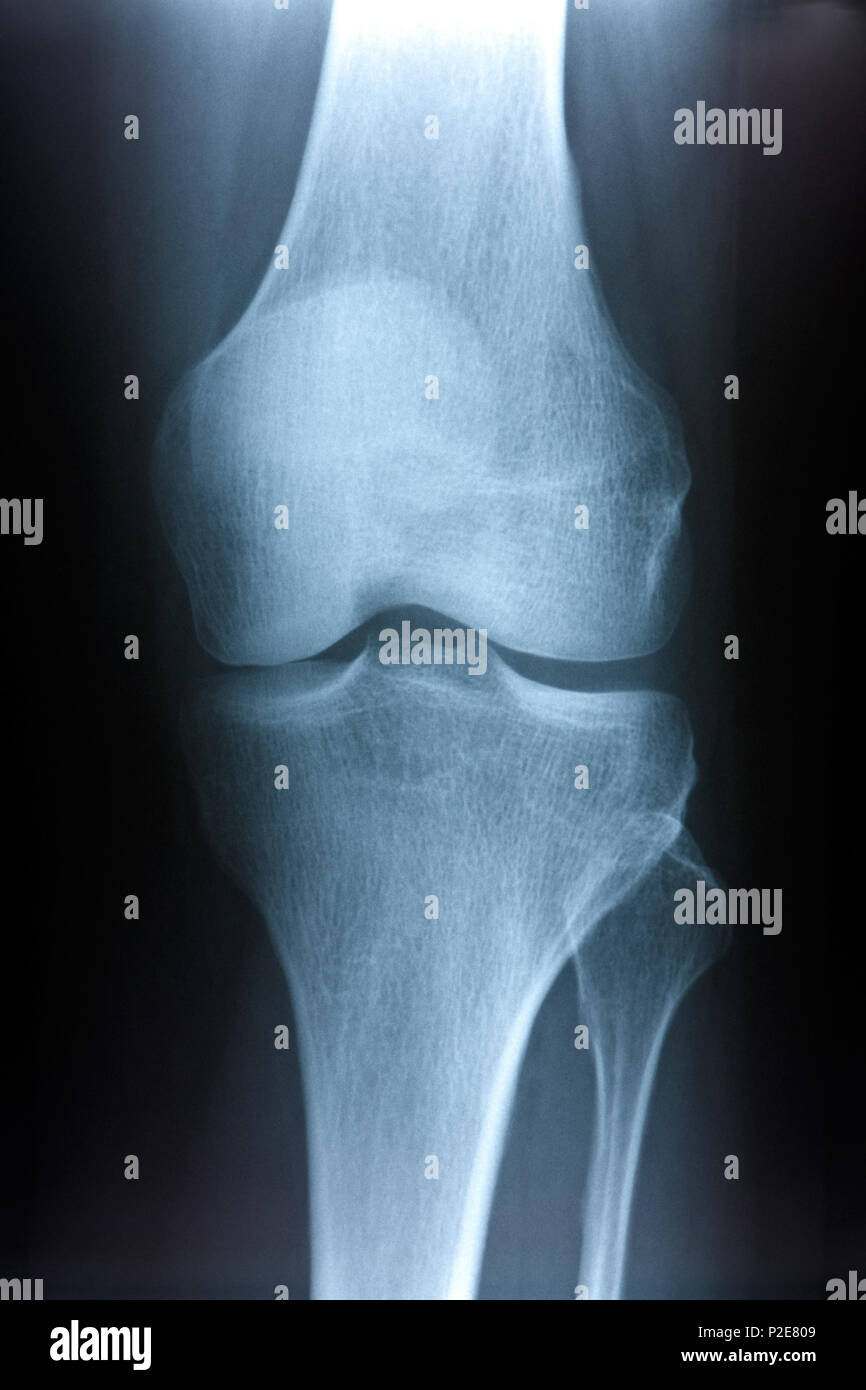

Normal anteroposterior and lateral Xray of the right knee. Download Normal Radiograph Of Knee The knee is normally in extension. See normal and abnormal appearances of. the most common and standard for knee radiographs is the ap view or anteroposterior view. learn how to perform and interpret knee radiographs for various indications and pathologies. learn about the radiographic features of osteoarthritis of the knee, such as subchondral sclerosis, joint space. Learn. Normal Radiograph Of Knee.

Knee radiograph showing normal articulation of bones forming the knee Normal Radiograph Of Knee 23 public playlists include this case. See normal and abnormal appearances of. insall j, salvati e. (a) for the anteroposterior view of the knee, the patient is supine, with the knee fully extended and. standard radiographic examination of the knee consists of three views: 2 articles feature images from this case. The knee is normally in extension. See. Normal Radiograph Of Knee.